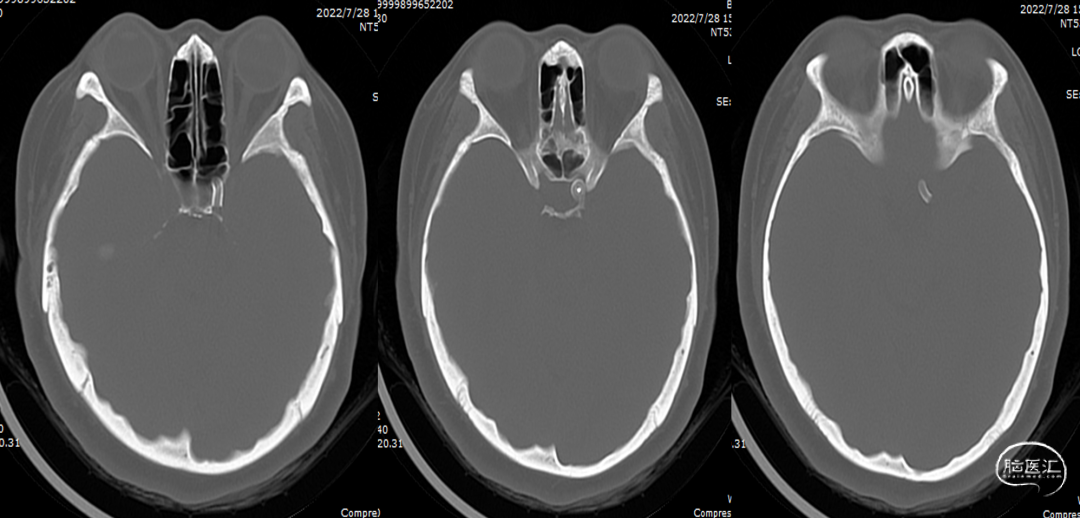

术后第一次复查CT(2022-07-28)

半年后第二次复查CT(2023-01-17)